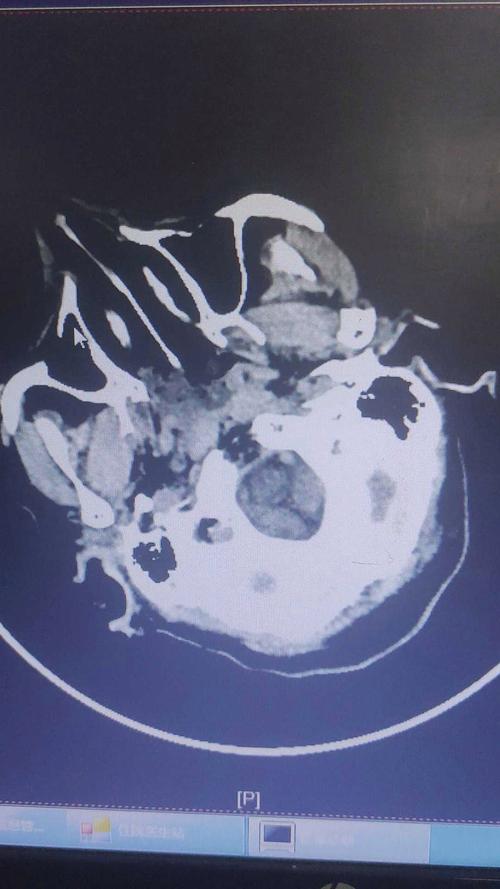

- 影像学检查(金标准):

- 头颅CT平扫: 可在早期排除脑出血,但发病6小时内可能看不到明显的梗死灶,仅见早期脑水肿的征象(脑沟变浅、脑室受压)。